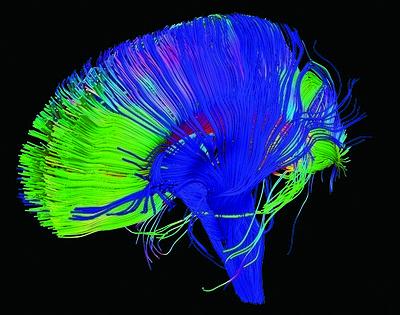

Diffusion tensor imaging (DTI) is a specialized MRI that is used to visualize and analyze the structural connectivity and organization of the brain's neural pathways (made up of white matter), as seen in the image below. DTI uses the movement of water molecules within brain tissue to infer the orientation, direction (meaning which way action potentials will move down these axons), and overall organization of these bundles of white matter.

ImageDTI imaging creates detailed and beautiful color coded images of white matter bundles. Image credit: NICHD/P. Basser